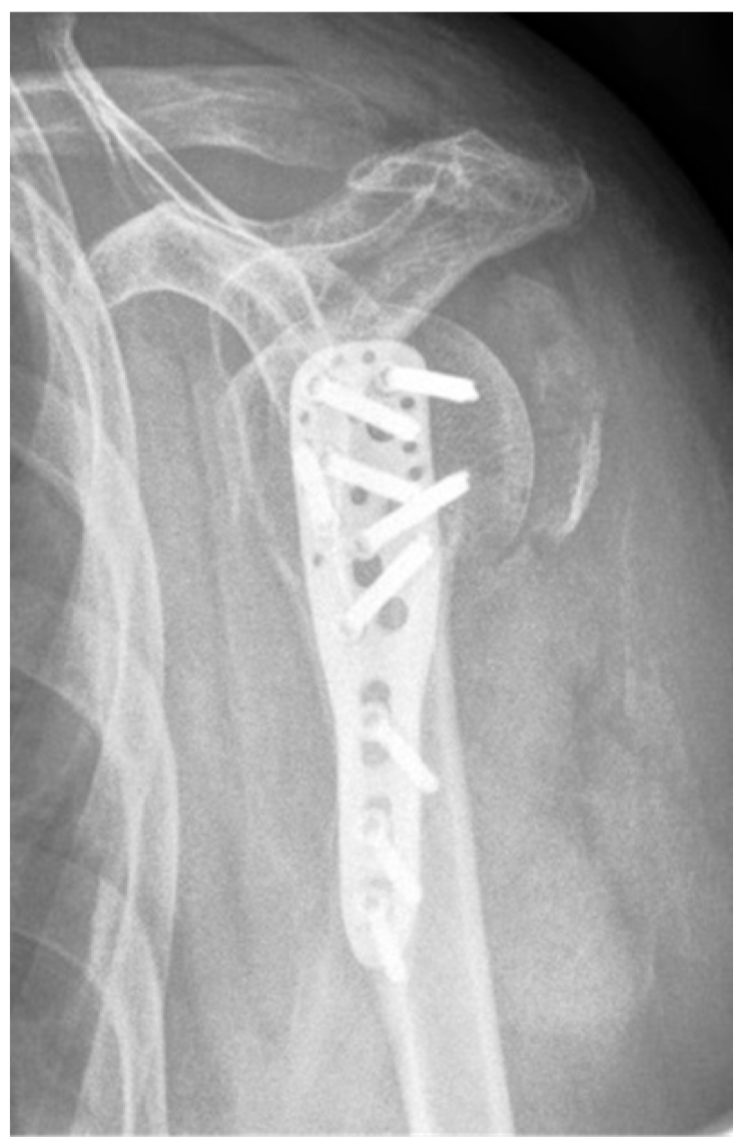

| Complication Type | Exemplary Images by X-rays or Pattern Images | Definition |

|---|---|---|

| 1 | ![]() | Complication Type 1 is defined by a mild, stable varus or valgus displacement (<20°) of the humeral head without resulting in a screw cutout through the humeral head cortex. |